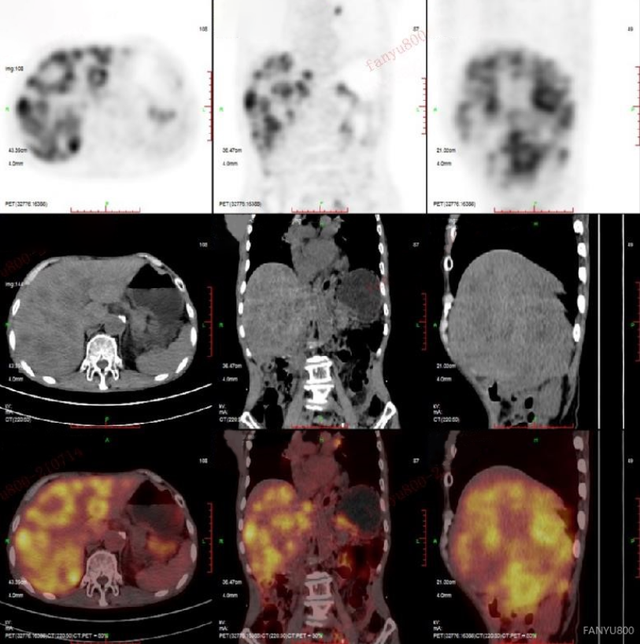

发布高建英主任petct在肿瘤远处转移中的临床应用